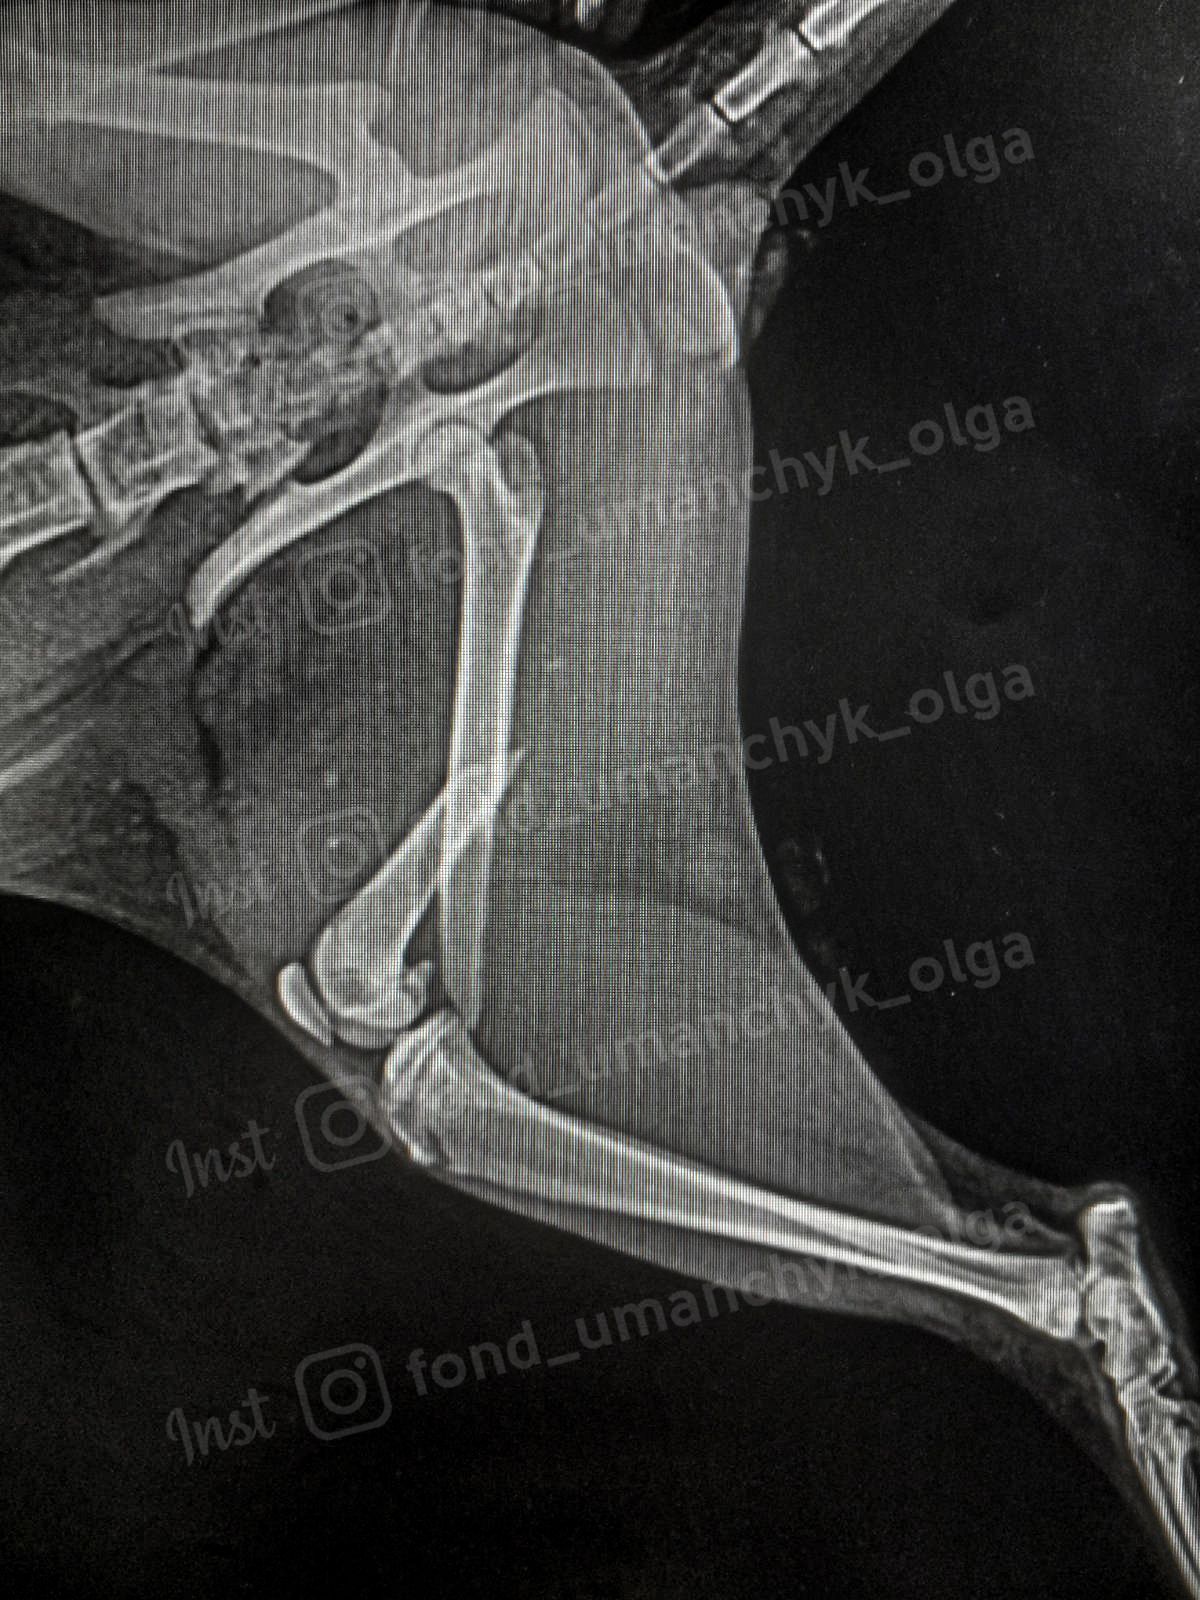

Волонтерка припускає, що маленьке кошеня міг хтось побити. У нього перебиті обидві задні лапки та таз, тому тварина не може пересуватися самостійно та відчуває сильний біль, який не можуть заглушити навіть знеболювальні.

Котика врятувати можна, але для цього треба провести три складні дороговартісні операції, щоб закріпити зламані кістки. За попередніми підрахунками, треба більше 20 тисяч гривень. У клініці, які взялася за порятунок кота, обіцяли почали лікування кота, якщо притулок внесе половину потрібної суми.

Якщо не провести операцію, то котик залишиться з інвалідністю та не виживе на вулиці. Якщо ви хочете допомогти маленькому Альберту, то зробити це можна за реквізитами нижче.